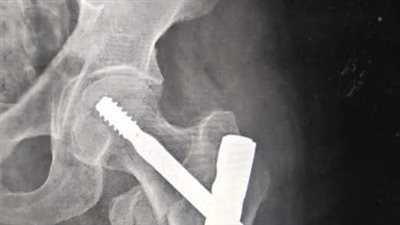

أظهرت المعاينة الأولية أن التصادم العنيف بين الميكروباص والجرار الزراعي أسفر عن مصرع أحد الركاب في الحال، بينما أصيب 8 أشخاص آخرين بإصابات تراوحت بين كسور مضاعفة، وكدمات وسحجات، إضافة إلى حالات اشتباه في ما بعد الارتجاج، وتم تقديم الإسعافات الأولية للمصابين في موقع الحادث قبل نقلهم إلى مستشفى العدوة المركزي لتلقي العلاج اللازم.